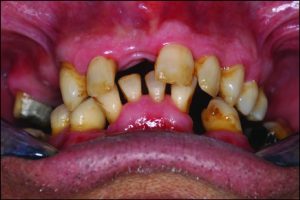

Occlusal discrepancies negatively affect the success of the prosthesis. In partially edentulous cases, due to reasons such as loss of teeth at different times or prolonged edentulism, the remaining teeth tend to tip, drift, or supra-erupt into the edentulous spaces (Figure 9-6).

Figure 9-6. In a patient who has been edentulous for a long time, positional changes in the natural teeth lead to occlusal discrepancies.